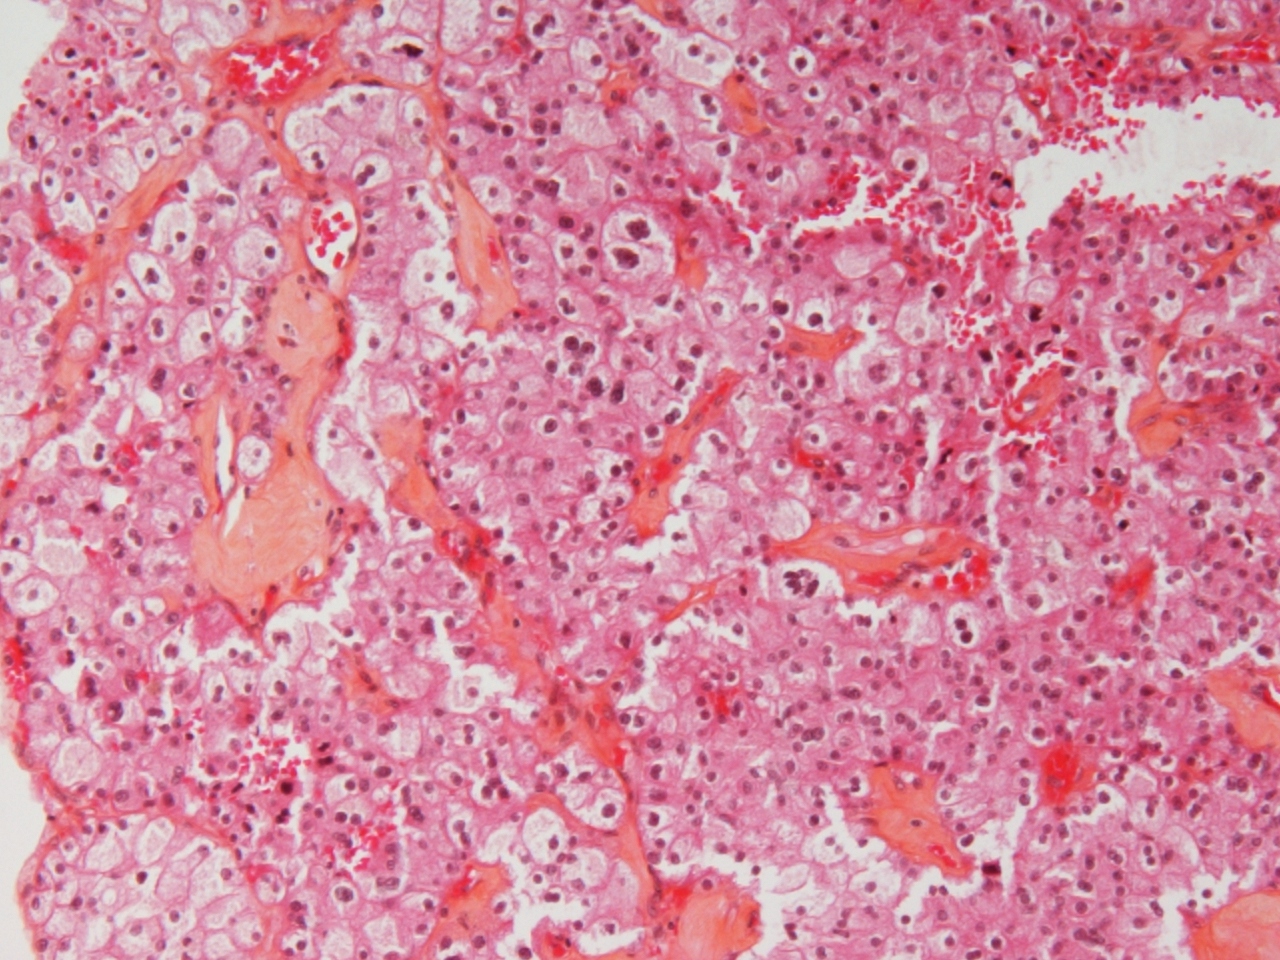

chromophobe RCC |

chromophobe |

just formal grading-I think it is chromophobe RCC |

chromophobe carcinoma